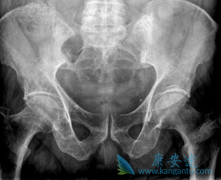

很多患者不清楚 什么是多发性骨髓瘤 ,下面来讲解下,多发性骨髓瘤(MM)是第二常见的血液系统肿瘤(占10%-15%),占血液系统肿瘤死亡人数的15%-20%。随着对骨髓瘤发病机制的进一步认识,其治疗方法也有了新的进展。虽然骨髓瘤目前仍无法治愈,但目前的 ...

患者患有多发性骨髓瘤的时候病情会不断的严重,而且这种骨髓瘤一定要采取手术的方法进行治疗早期的时候会出现非常明显的骨痛现象,会出现严重的损伤,那么患上 多发性骨髓瘤的症状 在早期是怎么样的?   多发性骨髓瘤的病情发展的速度是较为缓慢,有很 ...

什么是多发性骨髓瘤 ?多发性骨髓瘤是一种恶性肿瘤疾病,这种疾病的发生给患者的伤害很大,治疗多发性骨髓瘤的方法是以手术,放化疗。但是多发性骨髓瘤的分型复杂,不同类型对应的症状表现不同,从而直接影响治疗方案的选择。   按一般分型,可分为5 ...